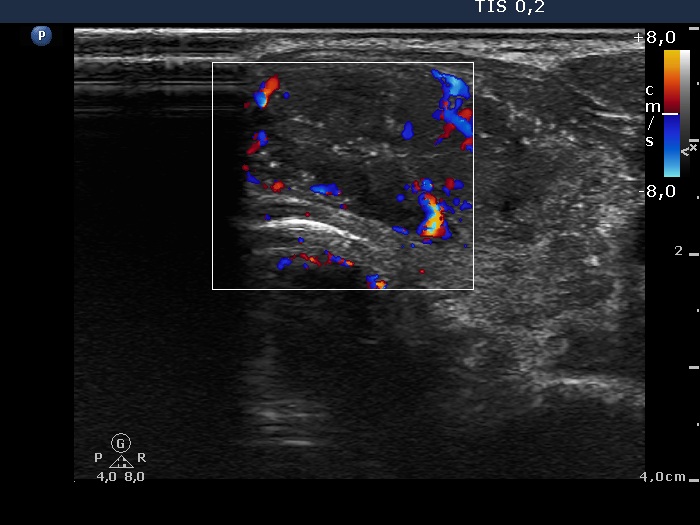

Follow-up examination 8 years later (4th and 5th rows of images):

Clinical data: The patient was referred for evaluation of a continuously increasing thyroglobulin level which resulted in 2.86 ng/mL, 5.74 ng/mL and 20.1 ng/mL, at the 2-yr, 5-yr and 7-yr follow up. Cytology of enlarged lymph nodes, multiple CT-scans and PET-CTs failed to reveal recurrence.

Palpation: There were two palpable, firm but freely moveable masses in the right and left submandibular area.

Hormonal examination: indicated euthyroidism with TSH 2.95 mIU/l on daily 125 microgram levothyroxine. Thyroglobulin was 15.4 ng/mL, anti-hTg was below 20 U/mL.

Ultrasonography revealed hypoechoic discrete lesions in both thyroid lobes. The lesions presented microcalcifications. Corresponding to the palpable mass in the right submandibular region, a reactive-type regular lymph node was found. There was an enlarged lymph node in the left submandibular region. The node had a regular hilum but displayed a heterogeneous pattern.

Cytology was performed from both lymph nodes and from the lesion in the left thyroid bed. FNA resulted in non-diagnostic report from the lesion in the left thyroid bed while cytology of the submandibular lymph nodes showed patterns of a benign, reactive-type lymph node.

Wash-out thyroglobulin levels were 0, 81.1 and 104.9 ng/mL, right submandibular lymph node, left thyroid bed lesion and left submandibular lymph node, respectively.